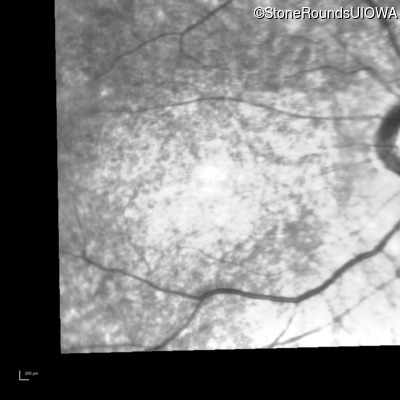

Infrared Fundus Photograph - Right - 10/200

Exemplar